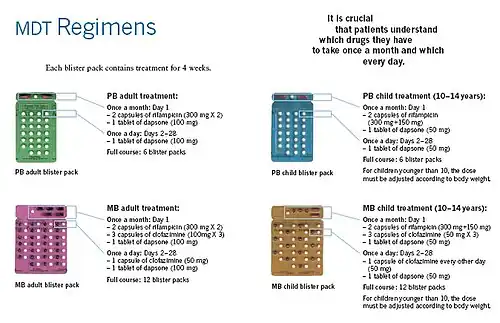

Leprosy is curable with multidrug therapy.[4] Treatment of paucibacillary leprosy is with the medications dapsone, rifampicin, and clofazimine for six months.[9] Treatment for multibacillary leprosy uses the same medications for 12 months.[9] Several other antibiotics may also be used.[3] These treatments are provided free of charge by the World Health Organization.[4]

Several leprostatic agents are available for treatment. A three-drug regimen of rifampicin, dapsone, and clofazimine is recommended for all people with leprosy, for six months for paucibacillary leprosy and 12 months for multibacillary leprosy.[9] Multidrug therapy (MDT) remains highly effective, and people are no longer infectious after the first monthly dose.[4] MDT is safe and easy to use under field conditions because it is available in calendar-labelled blister packs.[4] The treatment does pose compliance challenges for young children who find swallowing multiple solid pills difficult.[91] Post-treatment relapse rates remain low.[4]

The combination treatment accelerates treatment and decreases the chance of creating drug-resistant bacteria. All three drugs in the three-drug regimen are antibacterial, with rifampicin being the most potent. Rifampicin is scheduled monthly since it interferes with dapsone by inducing its increased metabolism.[92]

Resistance to the three-drug regimen has been reported in several countries, although the number of cases is small.[93] People with rifampicin-resistant leprosy may be treated with second-line medications such as fluoroquinolones, minocycline, or clarithromycin, but the treatment duration is 24 months because of their lower bactericidal activity.[94] Evidence on the potential benefits and harms of alternative regimens for drug-resistant leprosy is not available.[9]

Between 1995 and 1999, the WHO, with the aid of the Nippon Foundation, supplied all endemic countries with free MDT in blister packs, channeled through ministries of health.[4] This free provision was extended in 2000 and again in 2005, 2010, and 2015 with donations by the MDT manufacturer Novartis through the WHO.[133][4] At the national level, non-governmental organizations (NGOs) affiliated with the national program will continue to be provided with an appropriate free supply.[134]